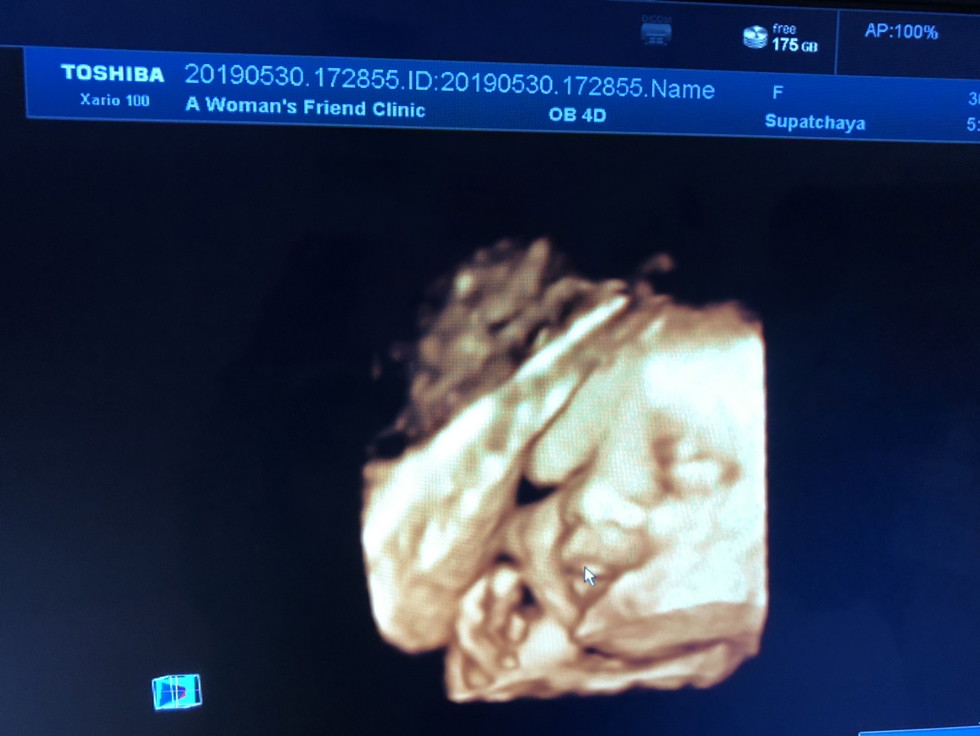

29wจ้า

29wแล้วค่ะ